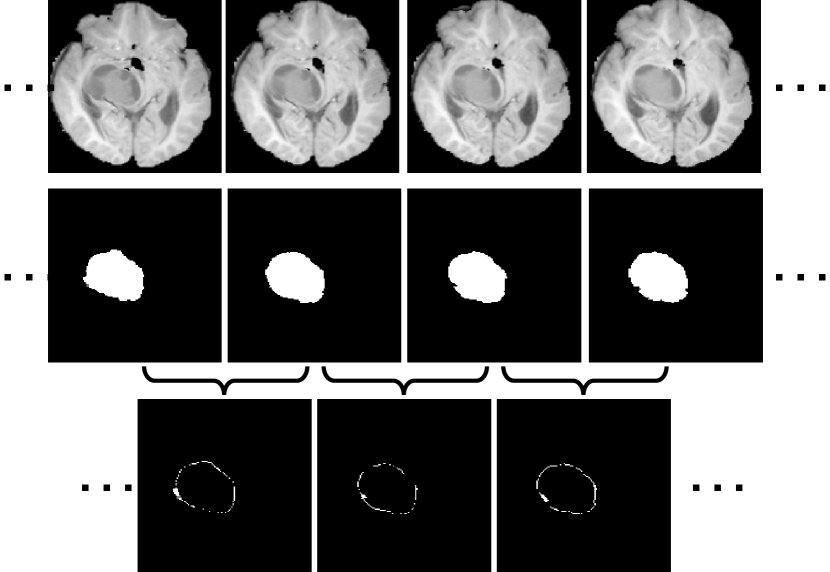

Refer to caption

Figure 1: Illustration of inter-slice context residual in 3D medical images. Top row: adjacent slices of a brain MRI image; middle row: corresponding masks of whole brain tumors; bottom row: inter-slice context residuals between adjacent slices (white: different; black: same).

However, it is difficult to capture the inter-slice context information in volumetric images with complex anatomical structures. Take a brain tumor in a magnetic resonance (MR) sequence for example. In Fig. 1, the first row shows four adjacent slices sampled from the sequence in which there is a brain tumor, the second row gives the ground truth tumor region in each slice, and the voxel-wise difference of the tumor region between any two adjacent slices, including extending outward regions or contracting inward regions, is displayed in the third row. We define such difference as the inter-slice context residual, which appears on or near the tumor surface and contains the essential and intriguing morphological information of the tumor, since we can use it, together with the tumor region in any slice, to reconstruct the shape of the 3D tumor. Intuitively, exploring the inter-slice context residual in a segmentation process must be beneficial to improving the accuracy. Unfortunately, since the tumor regions in two adjacent slices have the similar shape and size, the inter-slice context residual is usually tiny, and hence has never been characterized directly.